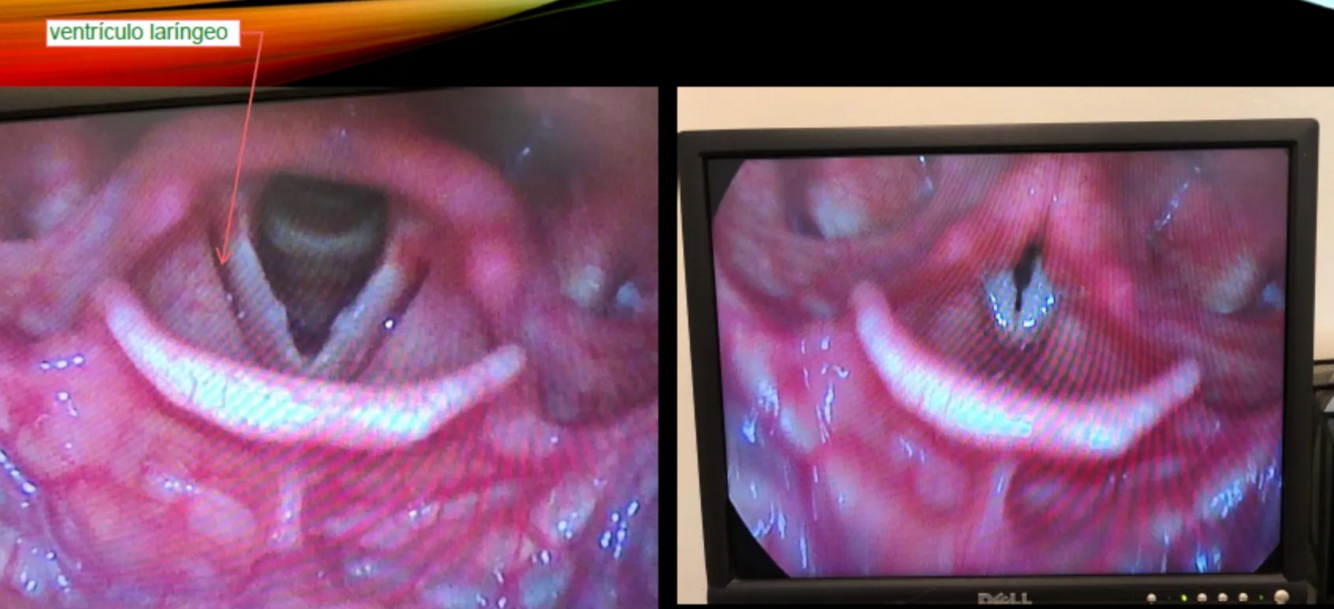

¿Qué métodos endoscópicos permiten observar la laringe?

A

• Flexible: nasofibrolaringoscopio

• Rígido: Telescopio de 70° (mejor visualización)

¿Para qué sirve la luz estroboscópica en laringoscopia?

Permite visualizar la ola vibratoria de las cuerdas vocales sobre el espacio de Reinke.

• Se identifica el ventrículo laríngeo entre cuerdas falsas y verdaderas (espacio oscuro entre las cuerdas)